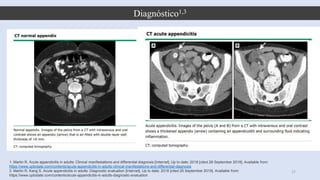

Tomografía computarizada 1

-Diámetro apendicular agrandado> 6

mm con una luz ocluida

- Engrosamiento de la pared

apendicular (> 2 mm)

- Aumento de densidad de grasa

periapendicular

- Apendicolito (visto en

aproximadamente el 25 por ciento de

los pacientes)

CAT Sensibilidad y

especificidad 94%;

LR+:15.6 LR–: 0.06 4